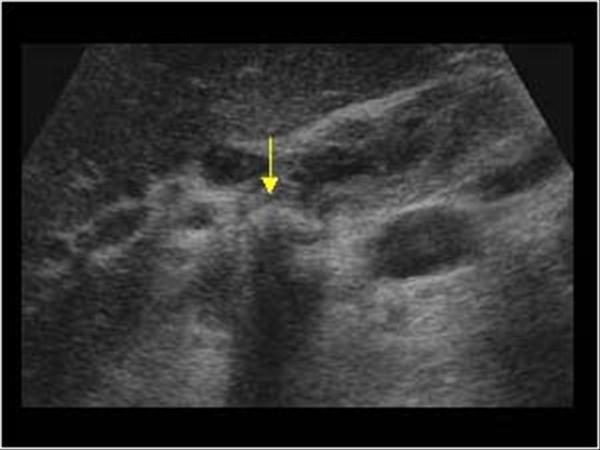

Which anatomical structure is located within the Lt Intersegmental fissure?

Left hepatic vein

Left Portal Vein

Ligamentum Teres

A groove that divides the Lt lobe of the liver into medial and lateral segment

Lt Intersegmental fissure